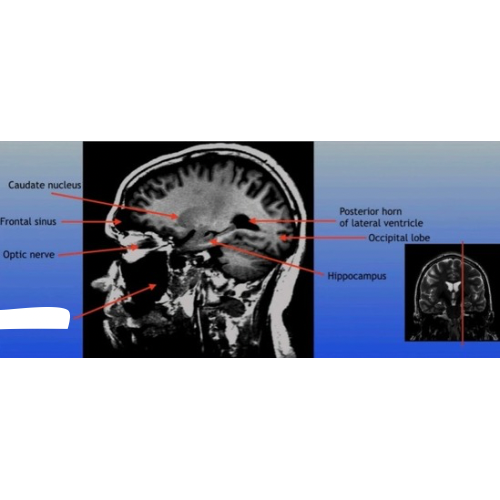

Caudate Nucleus

A C-shaped structure within the brain's basal ganglia, involved in various functions including motor control and learning.

Frontal Sinus

A paired cavity located within the frontal bone, above the eyes, that plays a role in sinus drainage and resonance of the voice.

Optic Nerve

The bundle of nerve fibers that transmits visual information from the retina to the brain. It plays a crucial role in the sense of sight.

Posterior Horn of Lateral Ventricle

The posterior part of the lateral ventricle, involved in the production and circulation of cerebrospinal fluid within the brain.

Hippocampus

A critical region in the brain associated with memory formation and spatial navigation, located in the medial temporal lobe.